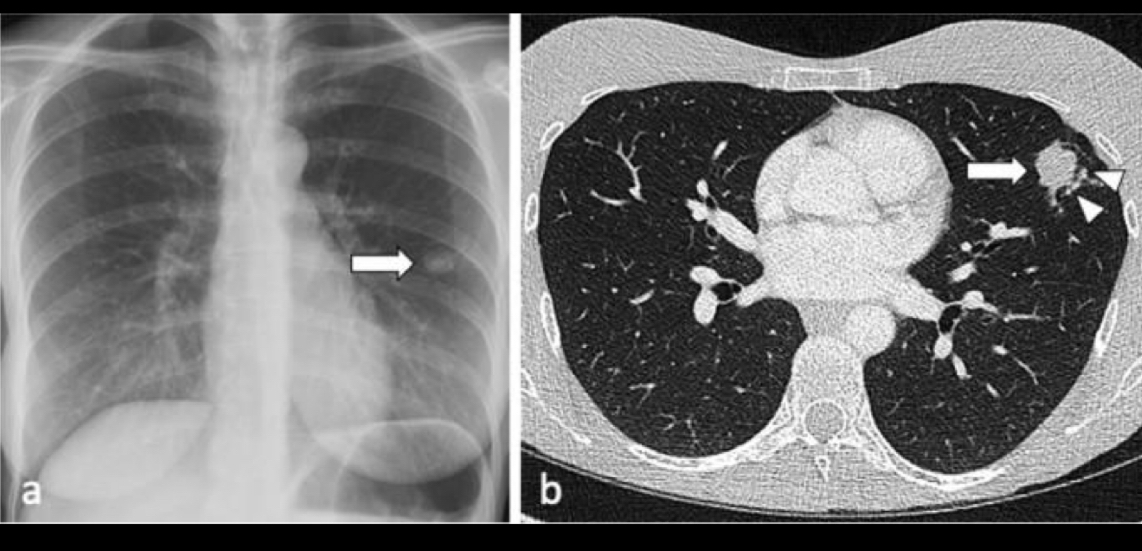

Que se ve en la primoinfecion

Nódulo solitario

si ves un nódulo solitario en q piensas

CÁNCER

si hay ganglios calcificados y nódulo en q piensas

nódulo de ghon q se asocia a ganglios calcificados en mediastino